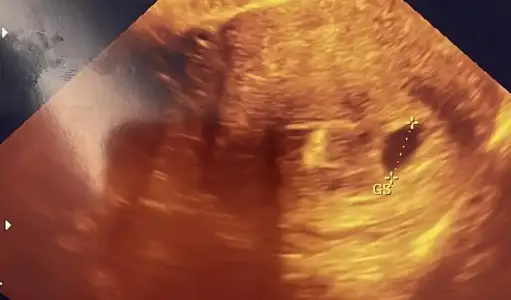

Benimde siyah beyaz olan 5. Haftamın ultrasonu. Renkli olan dün acilde doktorun çektiği ultrason yani 7. Hafta. Kesede büyüme var ama yolk saçını görmedi. Çok huzursuz oldum.

Renkli olanda neden olmaz o zaman? Aradan 2 hafta geçti neredeyse daha belirgin olması gerekmez miydi

Renkli olanda cekim yonu farkli

Renksiz olandaki gibi ortalamamis bence ultrasonu

Kenarda kaldigi icin oyle cikmis diye dusundum

Cunku hafif bile kaydirsa hemen goruntusu degisiyor ultrasonun